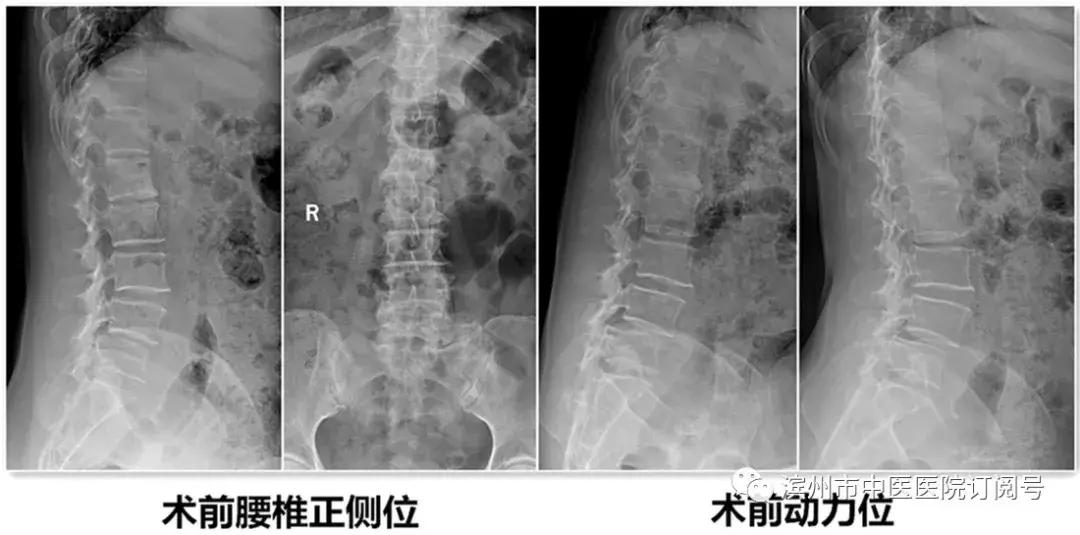

患者郭某,老年女性,因“反复腰部疼痛伴右下肢疼痛、麻木,不能行走”经多家医院诊治效果不好,遂来我院治疗。诊断为腰椎椎管狭窄并腰4/5椎体滑脱,入院后给予仔细查体及辅助检查。经检查该患者L4椎体退变性滑脱诊断较为明确,且伴有严重的椎管狭窄症状。由腰椎X线动力位片示腰椎不稳,腰椎融合术为最佳治疗方案。结合病人病情、年龄及身体条件,经腰椎间盘治疗中心团队反复论证,认为采取微创镜下融合术为最佳方案。刘维克主任介绍原本需要开放才能完成的手术现在微创下完成,需要攻克2个难点:一是需要在脊柱内镜下给予充分的减压,二是在微创通道下处理椎间盘和终板,并安全的植入融合器。

患者术后第3天带支具下床活动,症状基本消失,并行X线检查。见滑脱复位,且椎间隙高度恢复。